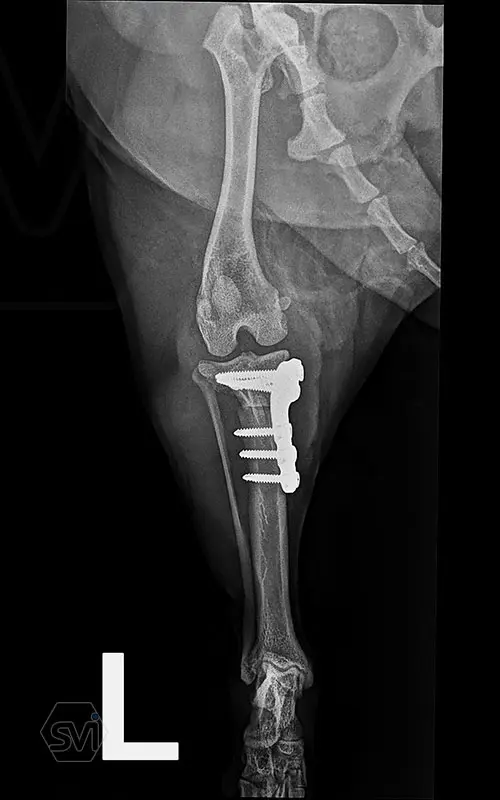

Multifunctional symmetrical long polyaxial locking plate - designed for the treatment of fractures close to joints

A special member of the polyaxial locking plate family is the multifunctional long plate, which is an extended version of the well-known symmetrical TPLO plate, with a 5-3 hole distribution. The plate also received a DCP hole to be able to create compression, and there is a mini-hole on the head end to facilitate the placement of the temporarily used K-nail. The burrs on the side facing the bone surface are intended to reduce the contact surface between the plate and the bone (limited contact).

The plate is a member of the large polyaxial locking family, suitable for 2.7-3.5-4.0 mm screws. We recommend it for fixaton of fractures close to joints, wedge osteotomies with axis correction (closing and opening), or for CWTO operations.